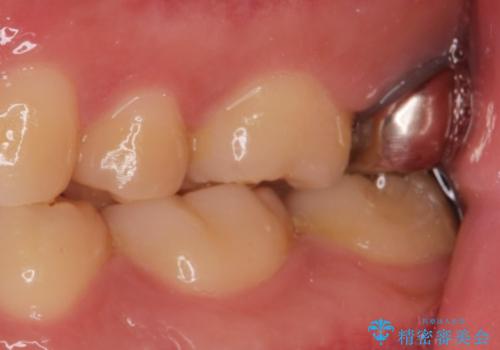

- 銀歯を良いものに変えたいとの事で来院。

過去に根の治療もされている歯だが土台が粗造なため根の治療からやり直しを行いゴールドクラウンにて治療を行いました。

また手前のはに虫歯があったためセラミックの詰め物で治療しました。

適合の良い被せ物が入りました。

ゴールドの被せ物は適合がよく虫歯の再発のリスクが低くなります。